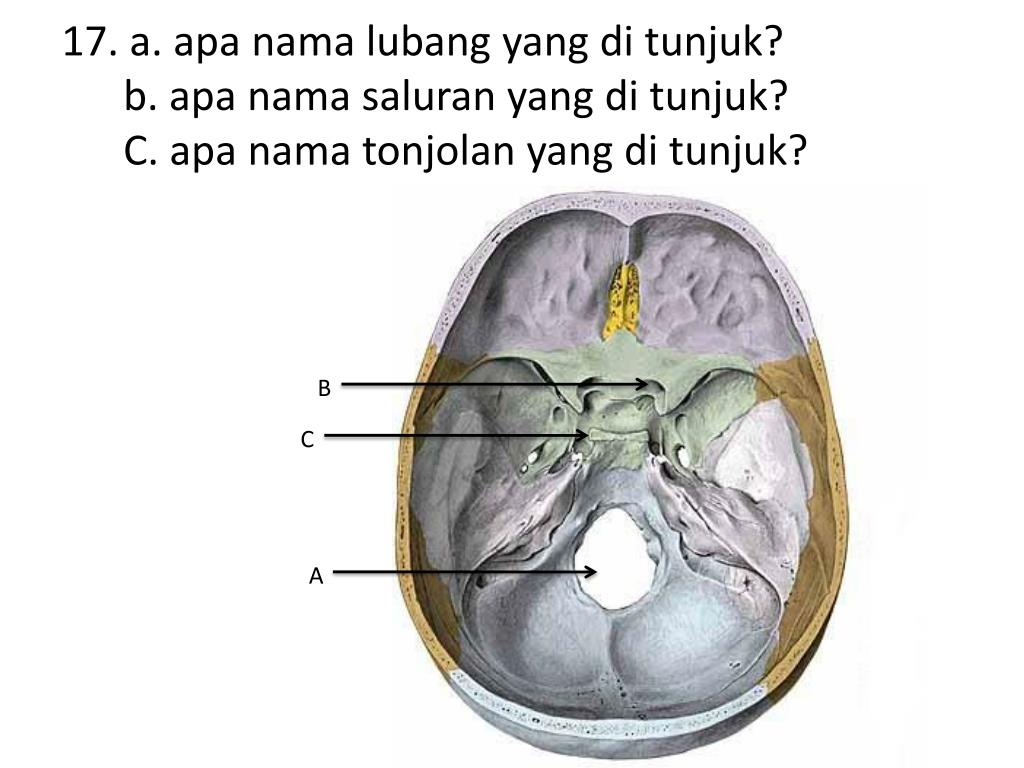

Анатомические детали: Фотографии топографии черепа с нижнего вида